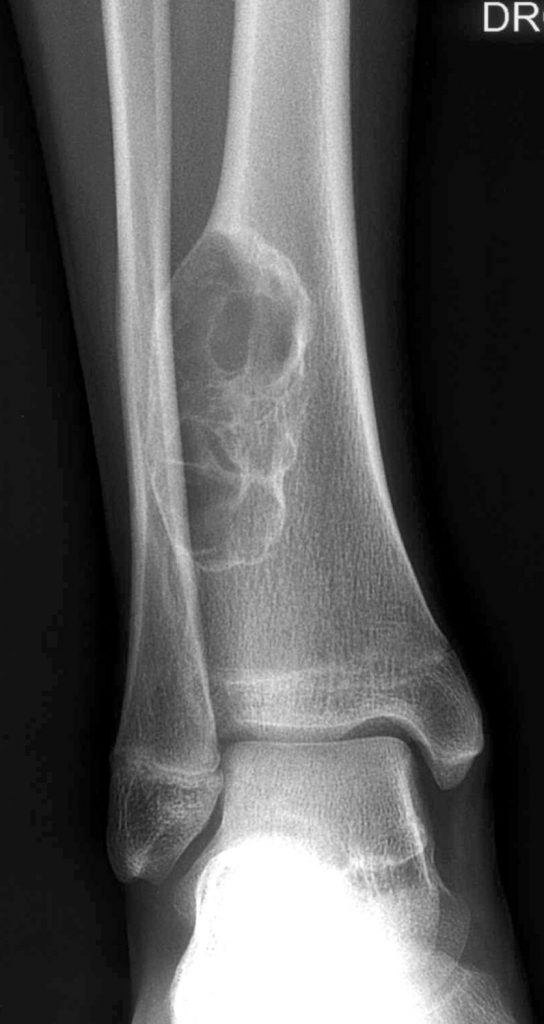

Fig. 120.1 Radiographie de face du tiers inférieur du tibia.

Lésion lentement évolutive, condensée en périphérie, à bords nets, intracorticale, témoignant d’une lésion bénigne et correspondant à un fibrome non ossifiant tibial inférieur.

Source : CERF, CNEBMN, 2022.